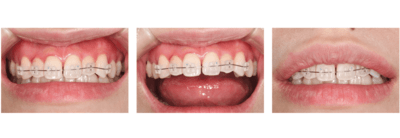

症例⑥

前歯の歯並びがきになる

| 年齢 | 20代女性 |

|---|---|

| 主訴 | 前歯の歯並びがきになる |

| 治療内容 | プチ矯正(上顎のみ) |

| 治療期間 | 2ヶ月 |

| 費用 | 165,000円(税込) (2022年2月現在) |

| リスク・副作用 | プチ矯正は全ての方に適応になるわけではありません。矯正中は器具が唇に接触するため口内炎ができやすくなります。歯が動かないなどで期間が長くなることもあります。 スペースをつくるために歯を削ることがあります。 |

| 治療方針 | 以前マウスピース矯正をしていたが、後戻りで前歯がやや前方にでてきてしまっています。 上顎下顎ともにあともどりがあり、歯と歯の間に若干スペースができている。 患者の希望が上顎だけだったので、下顎はそのままで、上顎のみ矯正をすることとした。 矯正は基本的にはスペースを作るため歯を削ることが多いが、今回のケースではスペースを閉じるだけなので、歯を削らずに行う計画を立てた。 |

矯正相談

【担当医師所見】

前歯の隙間が気になってきたとのこと。

CRを充填するか、矯正を行うかで選んでもらった。

矯正はおよそ3〜4ヶ月くらい(保定含む)で終わること、変色などの審美的なことに今後悩まなくて良いことから、矯正を選択した。

矯正後は保定装置を入れることをに同意を得た。

保定装置は上顎は舌側ワイヤー固定だとカリエスになりやすいので、マウスピース型の予定で考えた。

マルモ診断

・左上1番の唇側転位による正中離開

・左上2番の位置が上方へややあともどり

・OJはあるが、下顎との被蓋関係は問題なさそう

・左下12番間も若干スペースがあるが、そこは気にならないとのことで治療はしない

ブラケット・ワイヤー装着

まずはブラケットを装着。審美的になるべく阻害がないように、透明なブラケットを使用した。

2週間後

ワイヤーはまだたわみがあるが正中はやや閉鎖してきた。

更に2週間後

正中はほぼ閉じた。ワイヤーのたわみも無くなってきた。

もうすこし左上2が頬側に出てほしい。

完成。

保定もかねてワイヤー(1622SS)変更。

1ヶ月後

ブラケット除去。

同時に予定していた保定装置のマウスピース用の印象をおこなった。

正中離開、左上2の位置、被蓋関係、全ての改善をすることができた。しかもたったの2ヶ月!

翌日、ハードタイプ1ミリのマウスピースを保定装置として使用させるために作成しお渡した。